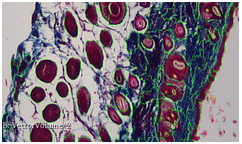

Microscopy images. Histological sections of regenerated skin after injury.

| Microscopy image |